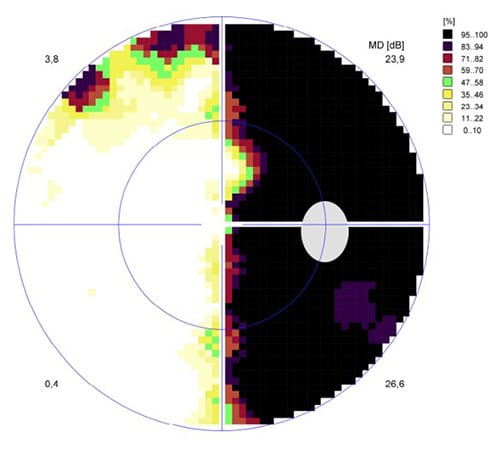

DEFECTOS DEL CAMPO VISUAL

Existen defectos del campo visual que son característicos de las afecciones neuro oftalmológicas como las hemianopsias (pérdida de la mitad del campo visual), las cuadrantanopsias (pérdida de un cuadrante del campo visual), los defectos altitudinales y alteraciones de la mancha ciega.